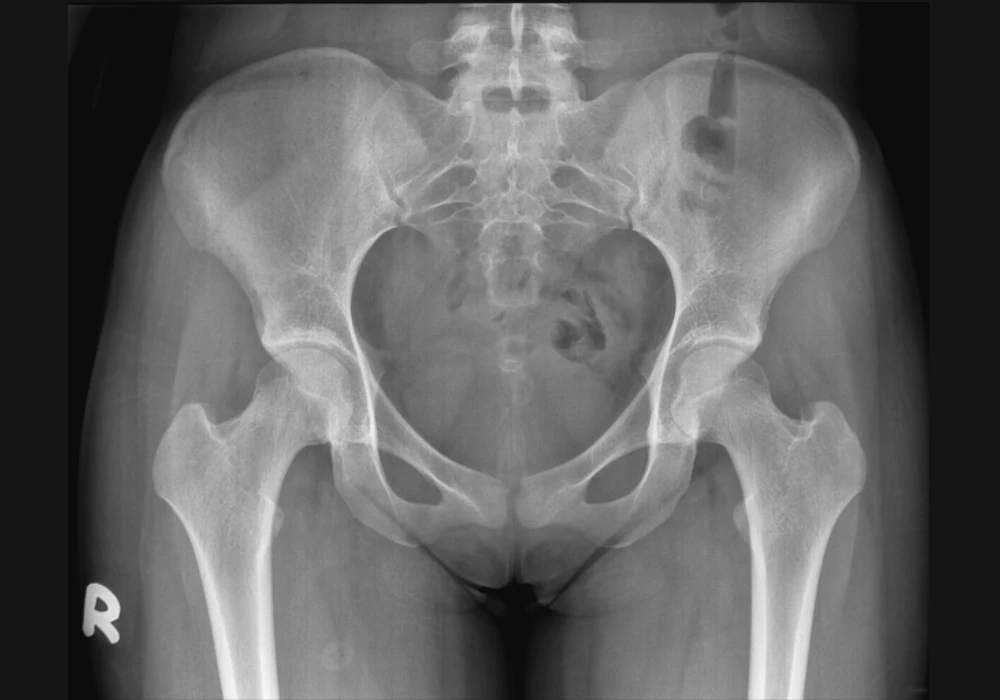

The main dataset included women around 50 years of age split across three groups: parous women with POP, parous controls and nulliparae. Three dimensional landmarks were placed on MRI scans to capture both the soft tissues that support the pelvic floor and the bones that form the pelvic canal. Configurations were standardised to focus on shape rather than size or position, and key patterns of variation were then identified.

When soft tissue and bone landmarks were assessed together, the three groups separated along the main shape patterns. POP cases tended to have a wider urogenital hiatus, extending partly below the ischiopubic outline. Nulliparous women showed a narrower hiatus positioned higher above the ischial bones. Parous controls sat between these two configurations. Within the combined analysis, the overall form of the bony pelvis also differed, with POP cases showing a pelvis that was shallower from front to back, wider side to side and shorter from top to bottom than the other groups.

Focusing only on bony landmarks strengthened the distinction between parous women with POP and parous controls. Along the main shape axis, the groups showed almost complete separation with strong statistical support. POP cases were characterised by a pelvis that was wider mediolaterally, shallower anteroposteriorly and shorter craniocaudally, with a wide subpubic angle. Parous controls had a taller pelvis with a relatively expanded anteroposterior dimension, producing a round to oval canal and a narrower subpubic angle. Nulliparous women spanned the range between cases and controls yet still differed from cases on the same axis.